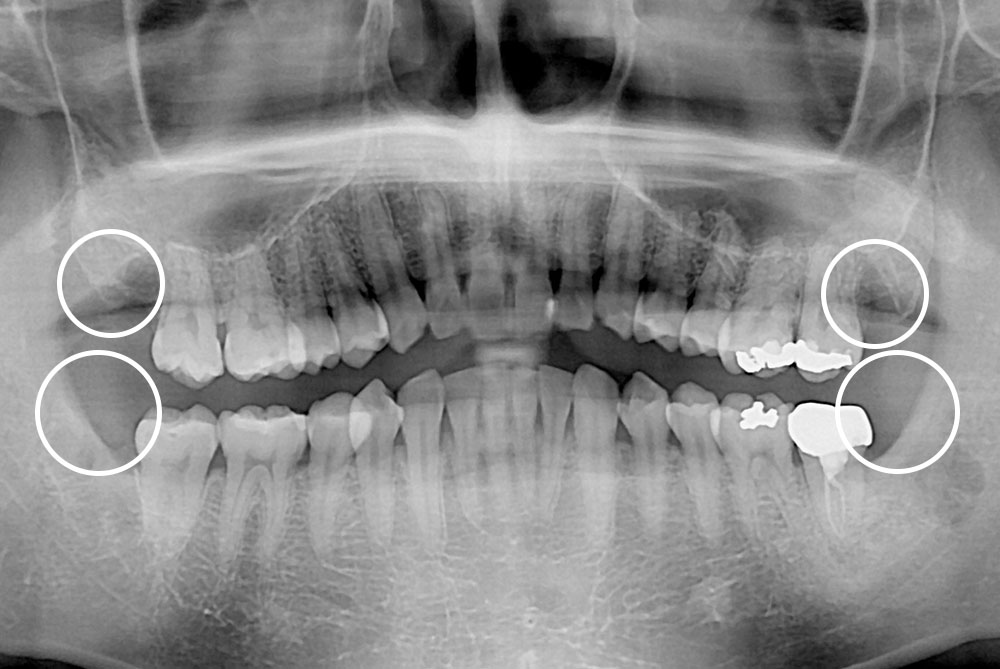

[사랑니] 매복 사랑니 발치

치료전 : 2019-08-06